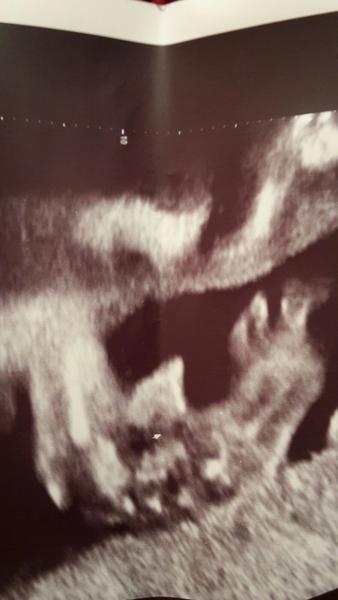

Je to holčička nebo chlapeček? Foto ultrazvuku

@estrellita tak podruhe potvrzena pipinka

Doktor si prave take nebyl jisty.Ale priklanel se 60% ke klukovi 🙂

@luccyj toto jsme videli na ultrazvuku na genetice ve 20 tydnu a pani doktorka rekla ze je to klucik. a intuice me zklamala celou dobu jsem byla presvedcena ze je to holcicka 🙂

@jsss tady mam utz nalevo syn, napravo nase dcera 🙂